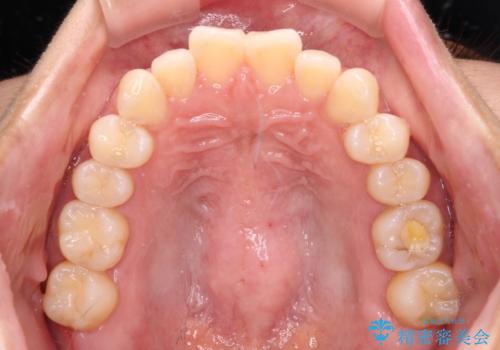

上顎前歯が捻れて前方に飛び出しており、下顎前歯もそれに沿うようにデコボコとなっていました。

IPR(歯と歯の間を削る処置)によりスペースを獲得して上下顎前歯のデコボコを改善し、飛び出している前歯が引っ込むように設定し、インビザラインにて矯正治療を行うこととしました。